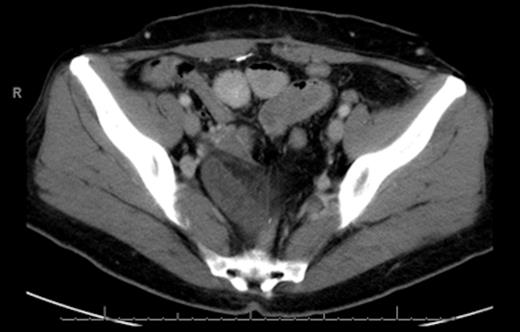

CT scan of the abdomen and pelvis revealed wall thickening and dilation of a few loops of small bowel located in the pelvis. We were not able to exclude closed loop obstruction (Fig. 1 & 2).